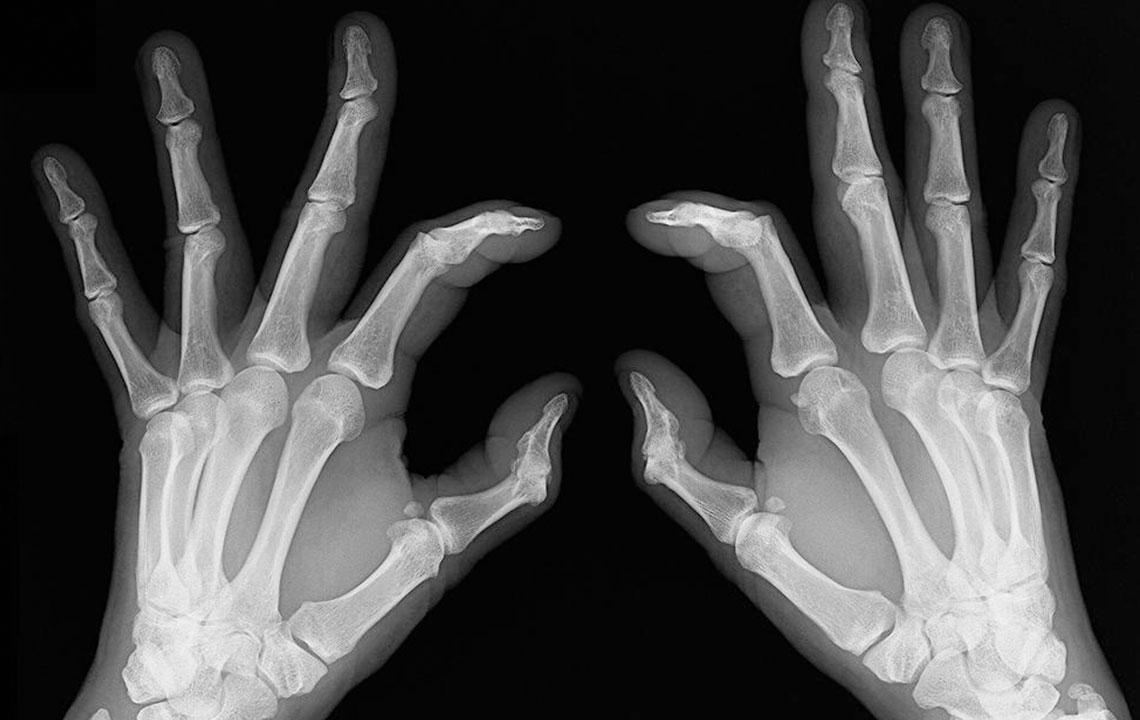

- Bone deformation: Arthritis also attacks the bones and makes them crooked and stiff. Look out for signs of any subtle changes in your joints and test them for pain levels.

- Inflammation: Sometimes rheumatoid arthritis symptoms show chronic flare up and can lead to swollen joints and inflammation. They are also symptomatic of lupus, so do consult your doctor before getting yourself treated for rheumatoid arthritis.